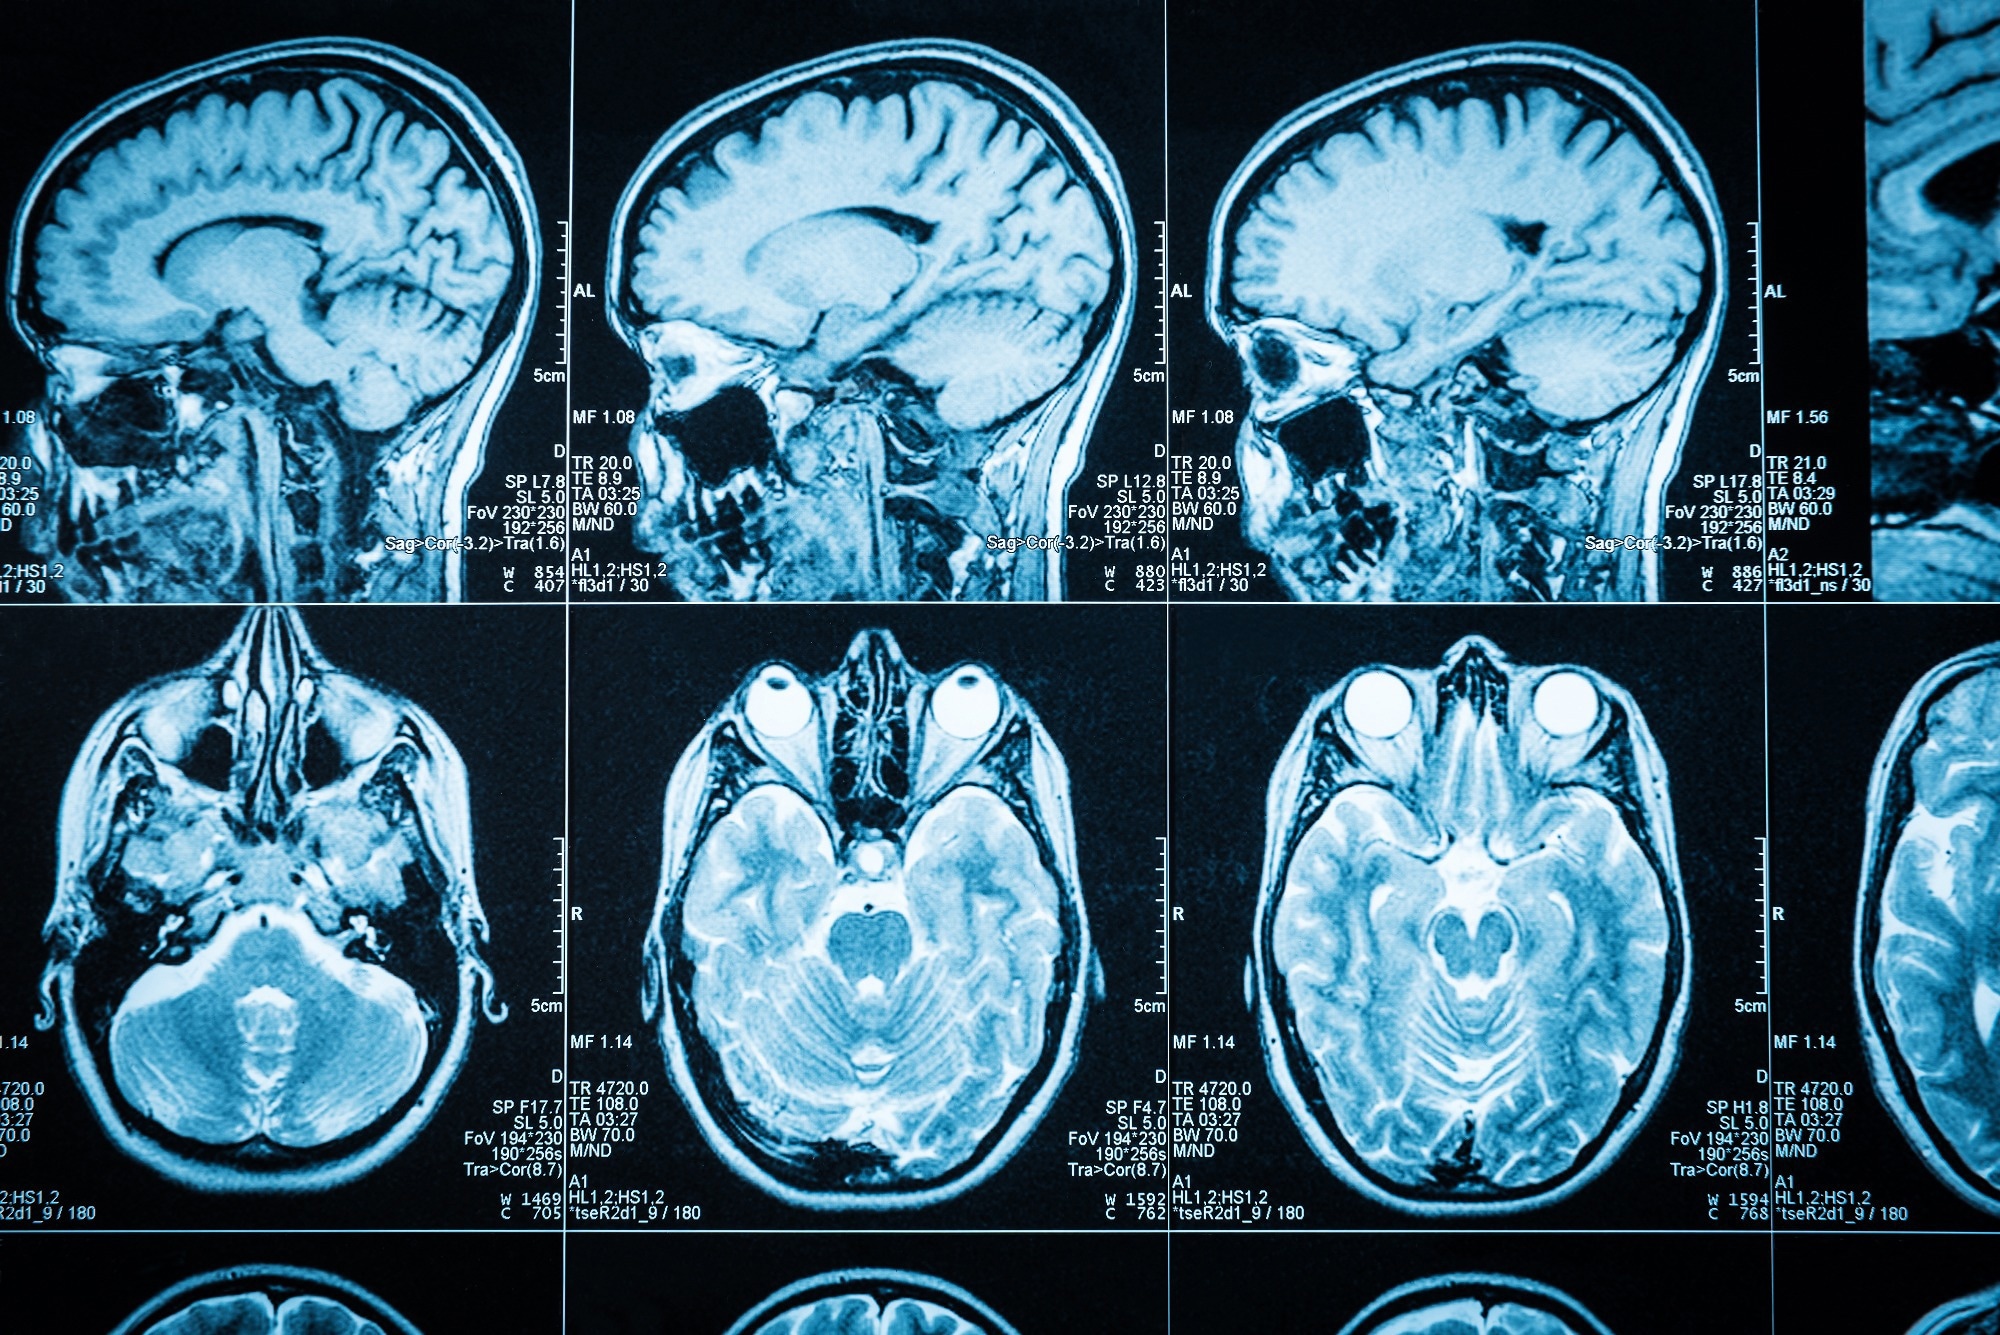

Arachnoid cysts (ACs) are benign, discrete pockets of CSF (cerebrospinal fluid) or CSF-like fluids, accounting for 1% of all intracranial space-occupying lesions. Commonly observed during childhood, ACs can be of two types - primary developmental cysts or secondary cysts.

Image Credit: Triff/Shutterstock.com

The diagnosis is commonly suspected on MRI with focal spinal cord displacement/buckling and, less frequently, on the direct sight of a cystic formation inside the spinal canal with signal patterns comparable to those of CSF.

With the widespread use of MRI, many lesions are now discovered by chance. MRI pinpoints the position and extent of spinal cord compression, but CT myelography (CTM) pinpoints the dural defect through which an extradural cyst communicates with the subarachnoid area.